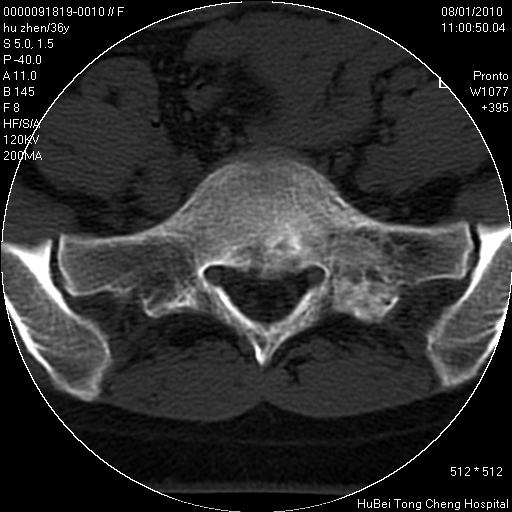

患者 女,36岁。右侧腰腿痛半月余。腰骶椎mr平扫偶然发现骶椎异常信号。

临床诊断:1)腰椎间盘突出症。2)骶椎肿瘤性病变?

骶椎ct平扫(层厚、层距均为5mm),图像如下:

考虑s1骨纤维异常增殖症。